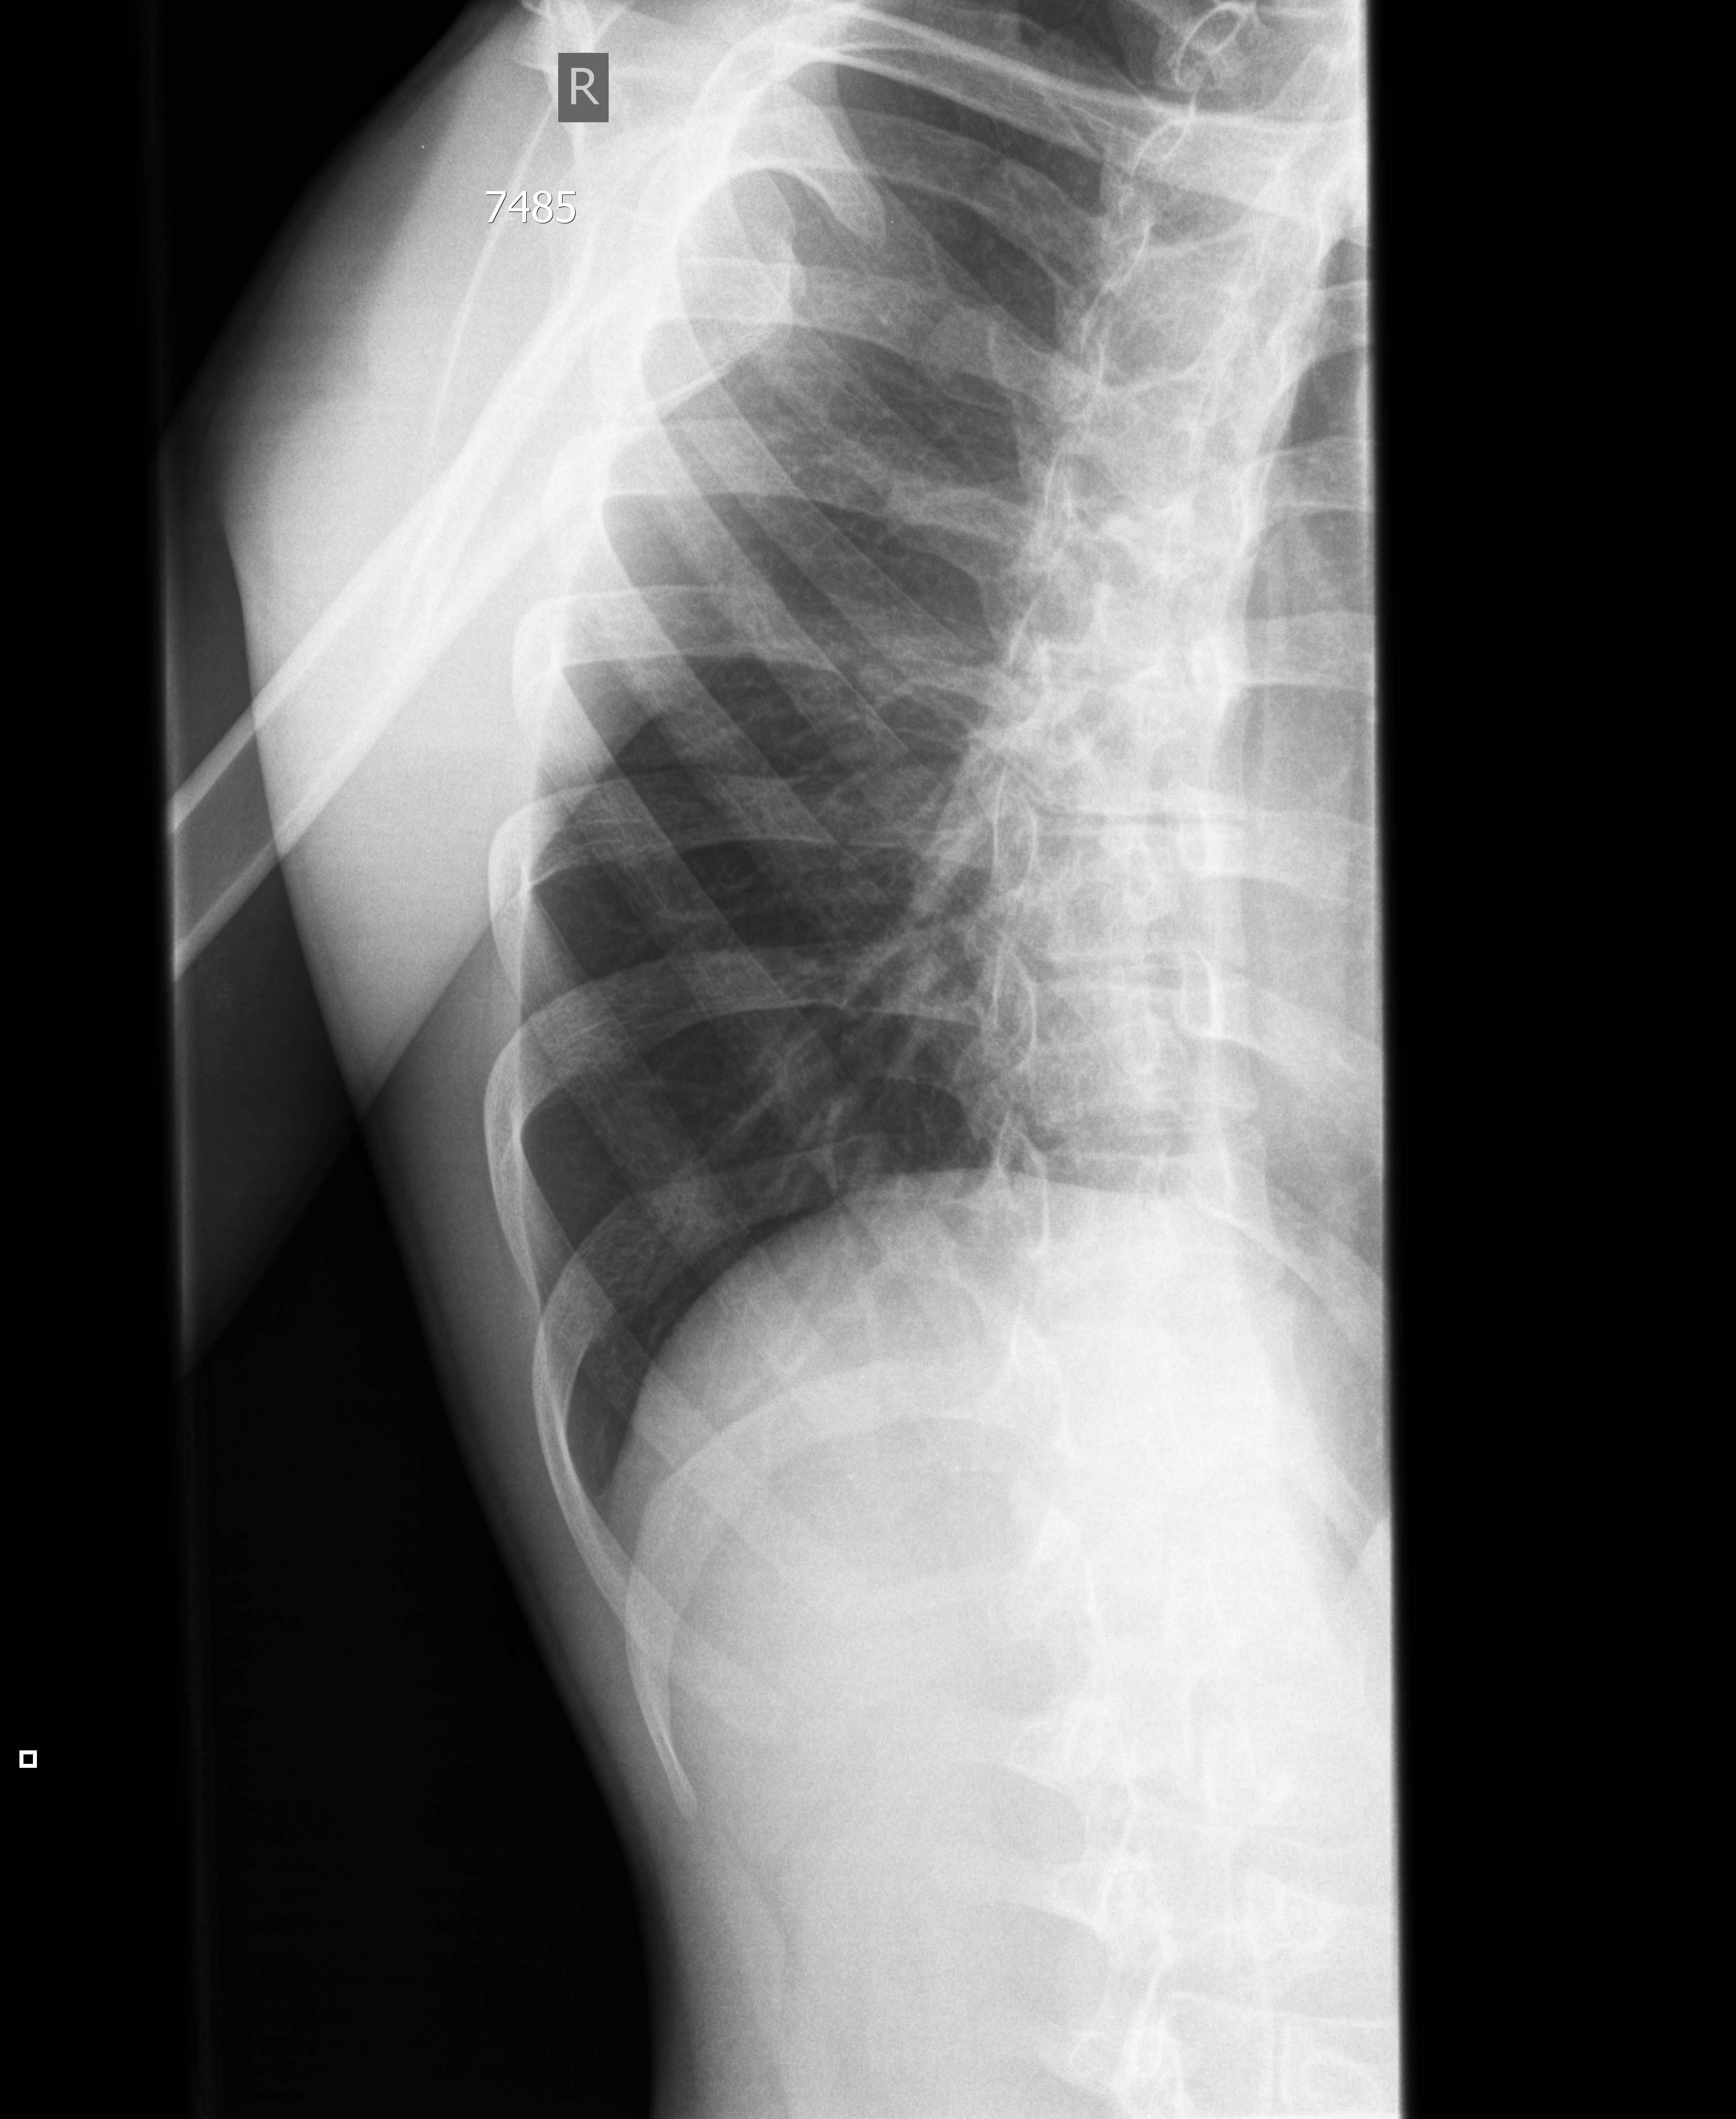

#5 Перелом ребер, УЗИ. Rib fracture, sonography. Šonkaulio lūžis.

19y M